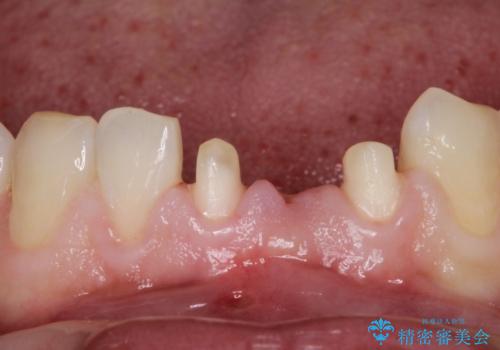

- 晩期残存した下顎乳中切歯の変色を主訴に来院されました。

後続永久歯は先天性欠如しており、下顎前歯のブリッジにて補綴治療を行なっております。

色調も周りの歯に合わせることができ、患者さんには満足していただきました。